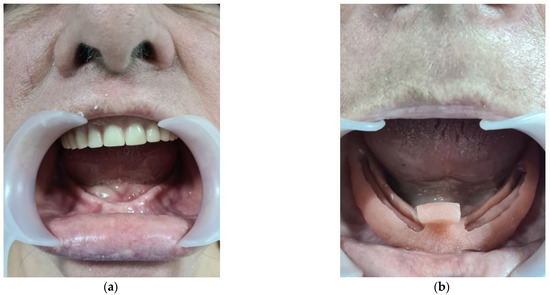

3.3. CASE REPORT 3